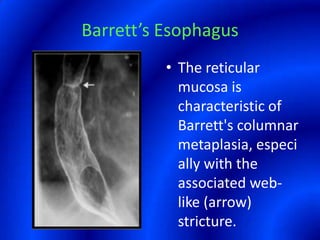

This document provides information about a barium swallow procedure. It begins with an introduction and overview of the embryology and anatomy of the pharynx and esophagus. It then describes the procedure itself, including preparation, technique, views obtained, and indications. Specific conditions that may be examined include pharyngeal and esophageal webs, foreign body impaction, scleroderma, dysphagia, mediastinal masses, and carcinoma. Diagrams are provided to illustrate normal anatomy and various pathological findings.